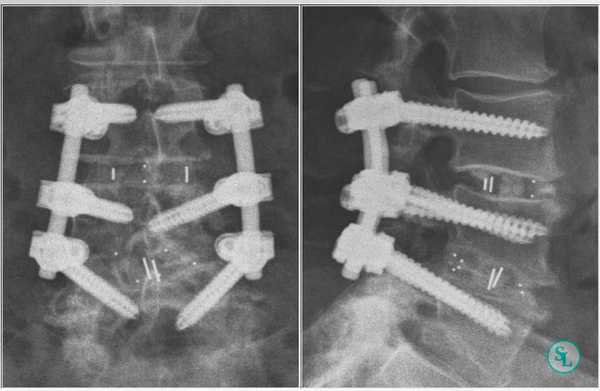

Кейджы межпозвоночных дисков поясничного отдела.

В преобладающем количестве подобные операции заключаются в достижении полного обездвиживания патологических уровней за счет прочного скрепления двух или более позвонков ригидными конструкциями. Это позволяет позвонкам с течением некоторого времени (от 3 до 6 месяцев) срастись между собой и образовать единый неподвижный костный блок. То есть, на прооперированном поле подвижность между позвонками будет заблокирована, а человек сможет нормально двигаться и ходить, не испытывая при этом боли и прочих неврологических расстройств.

Если выполняется одноуровневая фиксация, искусственно созданная обездвиженность будет неощутимой. При многоуровневой технике стабилизации, что требуется не так уж и часто, позвоночник в определенных местах утратит гибкость, из-за чего некоторые элементы движений станут выполняться несколько в ограниченной амплитуде.